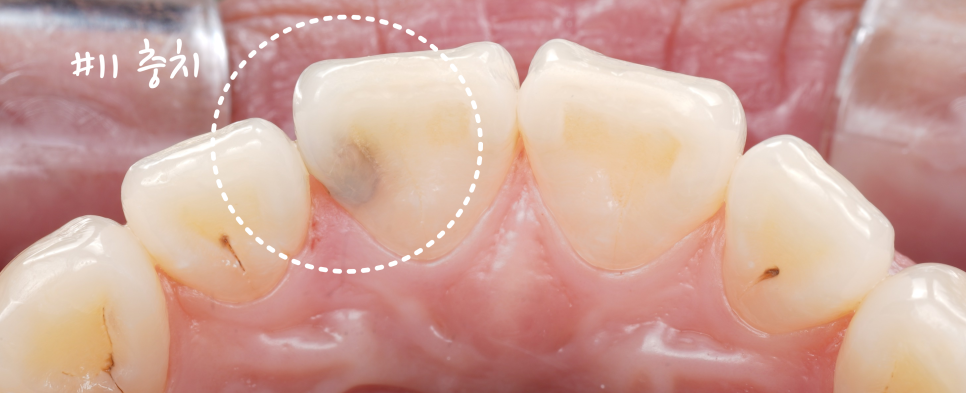

앞니 충치는 깊긴 했지만 바로 신경치료나 크라운이 필요할 정도는 아니었어요.

촬영일 : 250909

충치를 확인해 보니 깊긴 했지만, 신경치료까지 필요할 정도는 아니라고 판단했습니다.

그래서 조심스레 제거 후, 레진으로 마무리하기로 했어요.